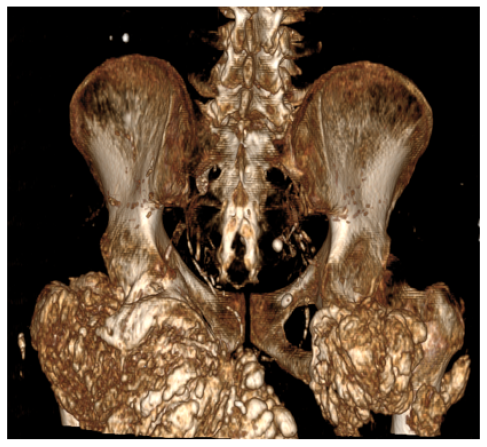

Tumoral Calcinosis in a Patient on Hemodialysis Involving Cervical Spine and Hips

Khadija Laasri, Kaoutar Imrani, Fatima Zahrae El Mansoury, Nabil Moatassim Billah and Ittimade Nassar. 6(5): 28-32.